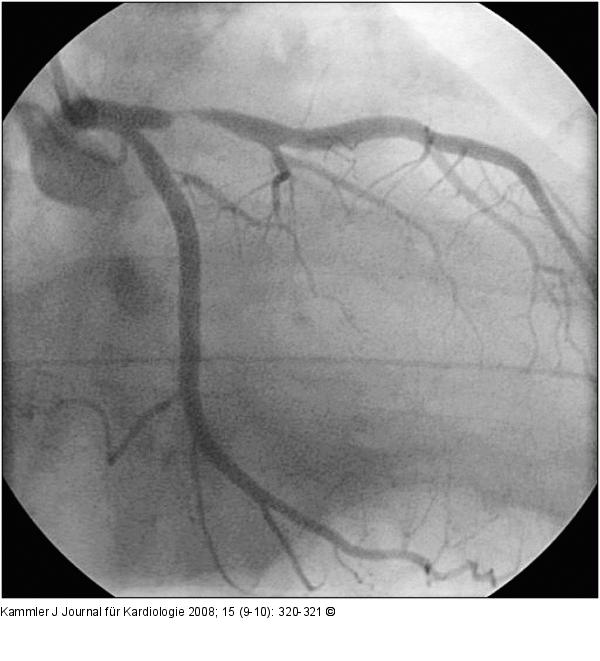

Abbildung 4: Transmurale Ischämie - Erstickungs-T-Wellen Akutangio vor PCI |

Abbildung 4: Transmurale Ischämie - Erstickungs-T-Wellen

Akutangio vor PCI |